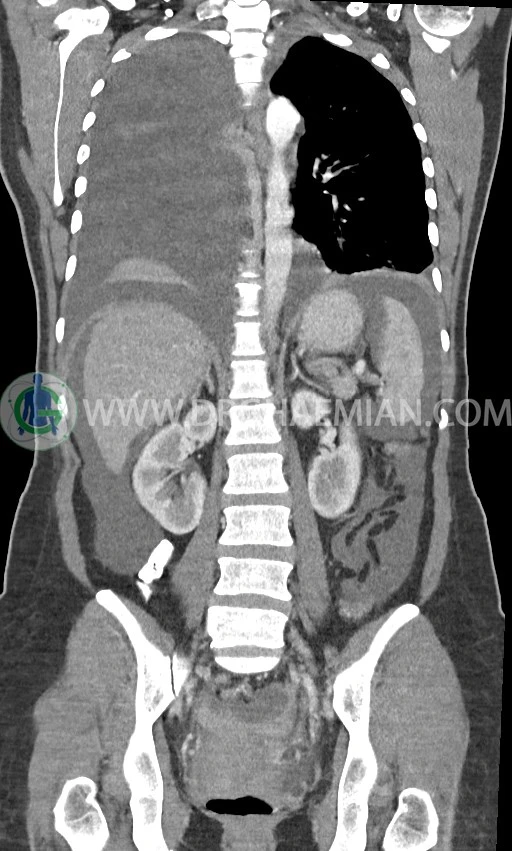

سی تی اسکن ریه با استفاده از اشعه ایکس تصاویر عرضی مقطعی از ریه و بالا تنه ایجاد می کند. در این کیس افیوژن پلور، لنفادنوپاتی، تخریب ریه سمت راست، توده پستان، آسیت و توده تخمدان دیده می شود.

در سی تی اسکن اسپیرال ریه، مدیاستن و شکم و لگن با کنتراست خوراکی و وریدی (مولتی دیدکتور 16 با مقاطع ظریف و بازسازی های ساژیتال و کرونال) :

pleural effusion قابل توجه دوطرفه همراه با passive collapse سگمان های بازال (با شدت بیشتر در سمت راست)

اسیت قابل توجه در حفره شکم و لگن

انفیلتراسیون تومورال در قسمت های مختلف اومنتوم (omental cake)، به ویژه در قسمت تحتانی حفره شکم و لگن

توده سالید – سیستیک به ابعاد 40x60mm در تخمدان چپ و به ابعاد 20x40mm در تخمدان راست و

لنفادنوپاتی فراوان در اطراف آئورت و IVC با حداکثر SAD= 25mm در دیواره دو طرف حفره لگن با حداکثر SAD= 20mm

مشهود است.